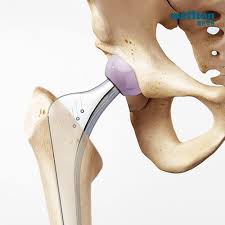

- 고관절 전치환술(Total Hip Arthroplasty, THA): 골관절염이나 류마티스 관절염, 골절 등에 널리 사용되는 방식으로, 관절 전체를 인공 관절로 교체합니다.

- 부분 치환술(Core Decompression 등): 골수 괴사 초기에 시행되며, 병변 부위만 최소 침습적으로 치료합니다.